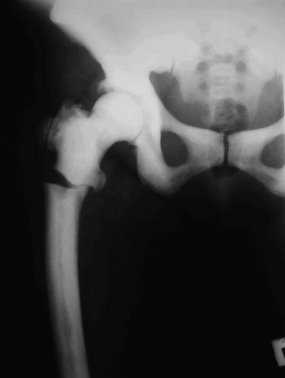

Остеопетроз описывается как синдром чрезмерной кальцификации костей, вызывающий мраморный вид с повышенной рентгенологической плотностью скелета (рис. 1, 2, 3).

Рис. 1. Перелом правой бедренной кости при мраморной болезни

Рентгеновская картина мраморной болезни очень своеобразна. Больше всего поражается основание черепа, позвонки, ребра, проксимальные концы бедренных костей и дистальные берцовых костей. Menee изменены плечевые кости и фаланги. Эпифизы несколько утолщены. Метафизы более всего изменены и имеют булавовидную форму. Кости — плотны и непрозрачны. Костномозговой канал виден резко суженным. Иногда на фоне плотной мраморной кости имеются широкие поперечные светлые полосы нормального строения кости (С.

На серин рентгенограмм костного скелета обнаружено: значительное уплотнение костей основания черепа, повышенная плотность костей таза, нижних конечностей, ключиц и ребер. Избыточное разрастание остеоидной ткани в области ростковых зон и нарушение костеобразования в этих отделах. Заключение рентгенолога — мраморная болезнь.

Свое название мраморная болезнь получила в связи с особой картиной рентгенограмм скелета, на которых обнаруживают необычно резкую плотность, гомогенность, бесструктурность костей, как будто они состоят из белого мрамора. Форма и размеры костей остаются нормальными. В костях черепа в первую очередь поражаются те, которые имеют хрящевое происхождение. Вместе со склерозом костной ткани отмечается сужение каналов черепных нервов, облитерируются придаточные пазухи носа. В теле позвонков центральная часть просветлена, а по ходу замыкающих пластинок образуются плотные широкие полосы.

Патологические переломы костей чаще возникают в подвертельной области бедренной кости, реже в других трубчатых костях и ребрах. Оскольчатые переломы встречаются редко, чаще плоскость перелома поперечная или косая. Дифференциальный диагноз в типичных случаях не труден. При маловыраженных или нетипичных рентгенологических изменениях дифдиагностику проводят с остеопойкилией, остеосклеротической анемией, остеомиелофиброзом, лейкозами, лимфогранулематозом, последствиями отравления свинцом, фосфором, особенно фтором, с некоторыми формами болезни Неджета, остеокластическими множественными метастазами, особенно рака предстательной железы. В детском возрасте остеосклероз может вызываться лекарственной терапией врожденного сифилиса, а также при гипервитаминозе «А» и «Д».

Рентгенологическая картина характеризуется диффузным тотальным уплотнением костей со специфическими изменениями позвонков, костей таза и метафизарных областей. Лабораторно - отмечается снижение уровня кальция и повышение уровня фосфора сыворотки крови.

Синонимы: мраморная болезнь, семейный остеопороз, врожденный диффузный остеосклероз. Диффузный остеосклероз или остеопороз значительной части костного скелета. Патогенез не выяснен. У половины больных клинических симптомов нет, болезнь диагностируют случайно при рентгенологическом исследовании по поводу перелома. Это заболевание доброкачественное, наследуется доминантно. Пораженные кости отличаются большой ломкостью. Сущность патологических изменений заключается в утолщении коркового слоя костей и сужении костномозгового канала, прогрессирующем остеосклерозе, уплотнении с одновременной хрупкостью костей и анемией. Наиболее выражены изменения в зонах роста, где бывают, видны колбовидные вздутия. В костях черепа суживаются отверстия со сдавленней нервов, из-за чего наступает глухота и слепота. Смерть может наступить при явлениях нарастающей анемии или от септикопиемии, источником которой являются гнойные остеомиелиты, развивающиеся как следствие патологических переломов. Когда в процесс вовлекается миелогенная ткань, заболевание принимает злокачественный (по течению) характер, проявляющийся в грудном возрасте задержкой роста, спонтанными переломами, значительной анемией, увеличением печени и селезенки, слепотой, тяжелым остеомиелитом. Тип наследования аутосомно-рецессивный. Прогноз неблагоприятен. Смерть в раннем возрасте из-за недостаточности костного мозга и геморрагического синдрома. На рентгенограммах пораженные кости имеют бесструктурное, как бы мраморное изображение, костномозговые пространства сужены, остеосклероз выражен в области длинных трубчатых костей, позвонков, таза.